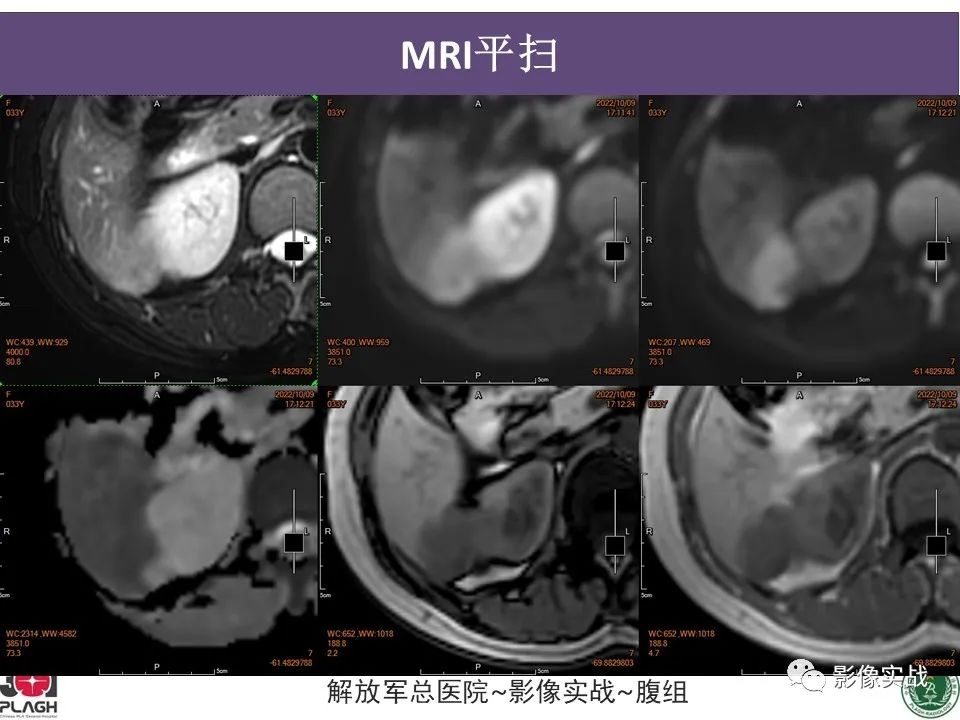

【病例】肝内胆管细胞癌1例MR影像-3

【病例】肝内胆管细胞癌1例MR影像-4